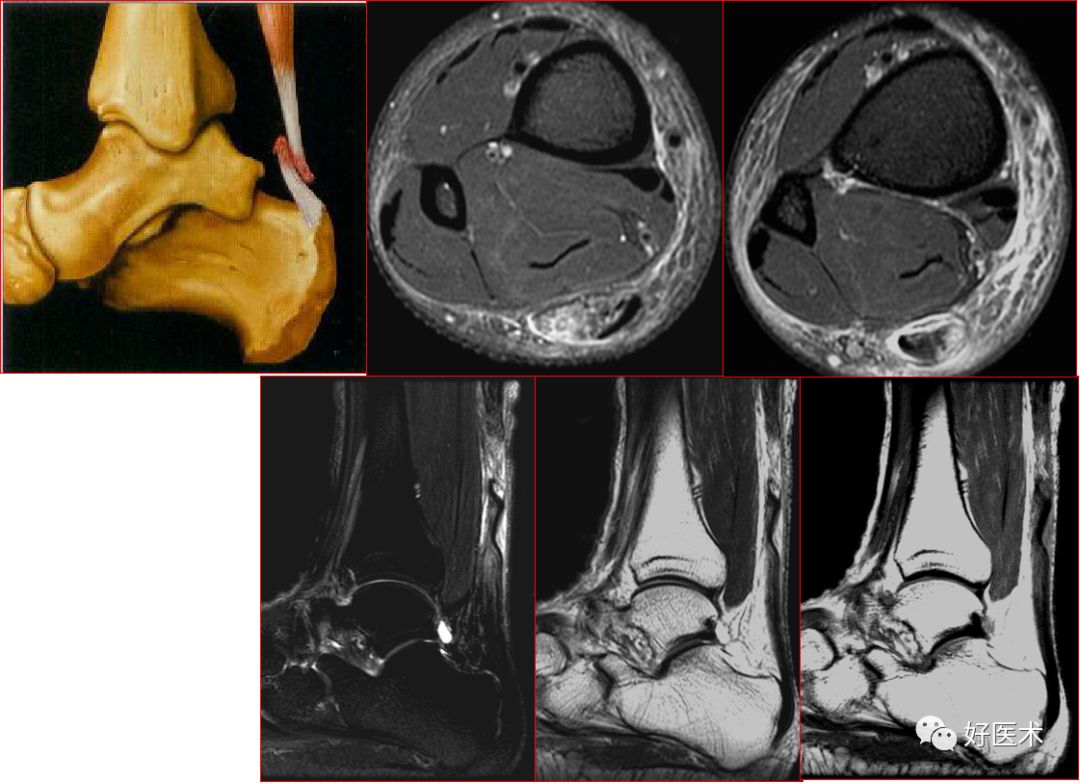

三角韧带

踝关节内侧韧带又称三角韧带,为强劲的三角形纤维束。上方附着于内踝尖及其前后缘;浅层纤维为胫舟部,前行附着于舟骨粗隆,部分与跟舟足底韧带的内侧面融合;中间部为胫跟部,下方附着于载距突;后部为胫距后部,纤维附着于至距骨内侧面和内侧结节。

三角韧带撕裂